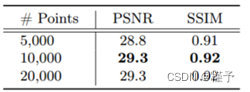

如2.2节所述,3D点被投影到2D成像面板,用于从视图的特征图中查询其视图特定特征。在本节中,我们正式引入投影函数φ。如图4所示,给定世界坐标系中的点,(WCS,下标w),我们首先将其从WCS转换到扫描仪坐标系(SCS,下标s),然后将其从SCS投影到面板坐标系(PCS);最后,获得其在PCS中的二维投影坐标,用于视图特定特征查询。对于简单的公式,我们假设成像面板与SCS的z方向正交,面板中心到PCS原点的偏移为零。

旋转。如图4a所示,给定坐标为pw = [xw,yw,zw] T的点定义在WCS中,我们首先通过旋转矩阵R(α)将pw从WCS变换为SCS,并获得其SCS坐标ps = [xs,ys,zs] T:

其中α是CT扫描仪的旋转角度。

投影。如图4b所示,假设从扫描器源O到成像面板的中心O′的距离为φ 00 ′ = d。投影矩阵A定义为:

图4.(a.)从世界坐标系(3D)到扫描仪坐标系(3D)的旋转。(B.)从扫描仪坐标系(3D)到面板坐标系(2D)的投影。

然后,我们通过投影矩阵A将ps投影到成像面板,并获得投影齐次坐标:

最后,我们得到PCS中的投影点p ′ = [u,v],其中u = dxs zs和v = dys zs。总之,对于WCS中的点p = [x,y,z] T,投影点p ′ = [u,v] T被公式化为:

其中β表示成像参数(距离、偏移等),H:R 3 → R 2是将p ′的齐次坐标映射到其笛卡尔坐标的齐次除法。